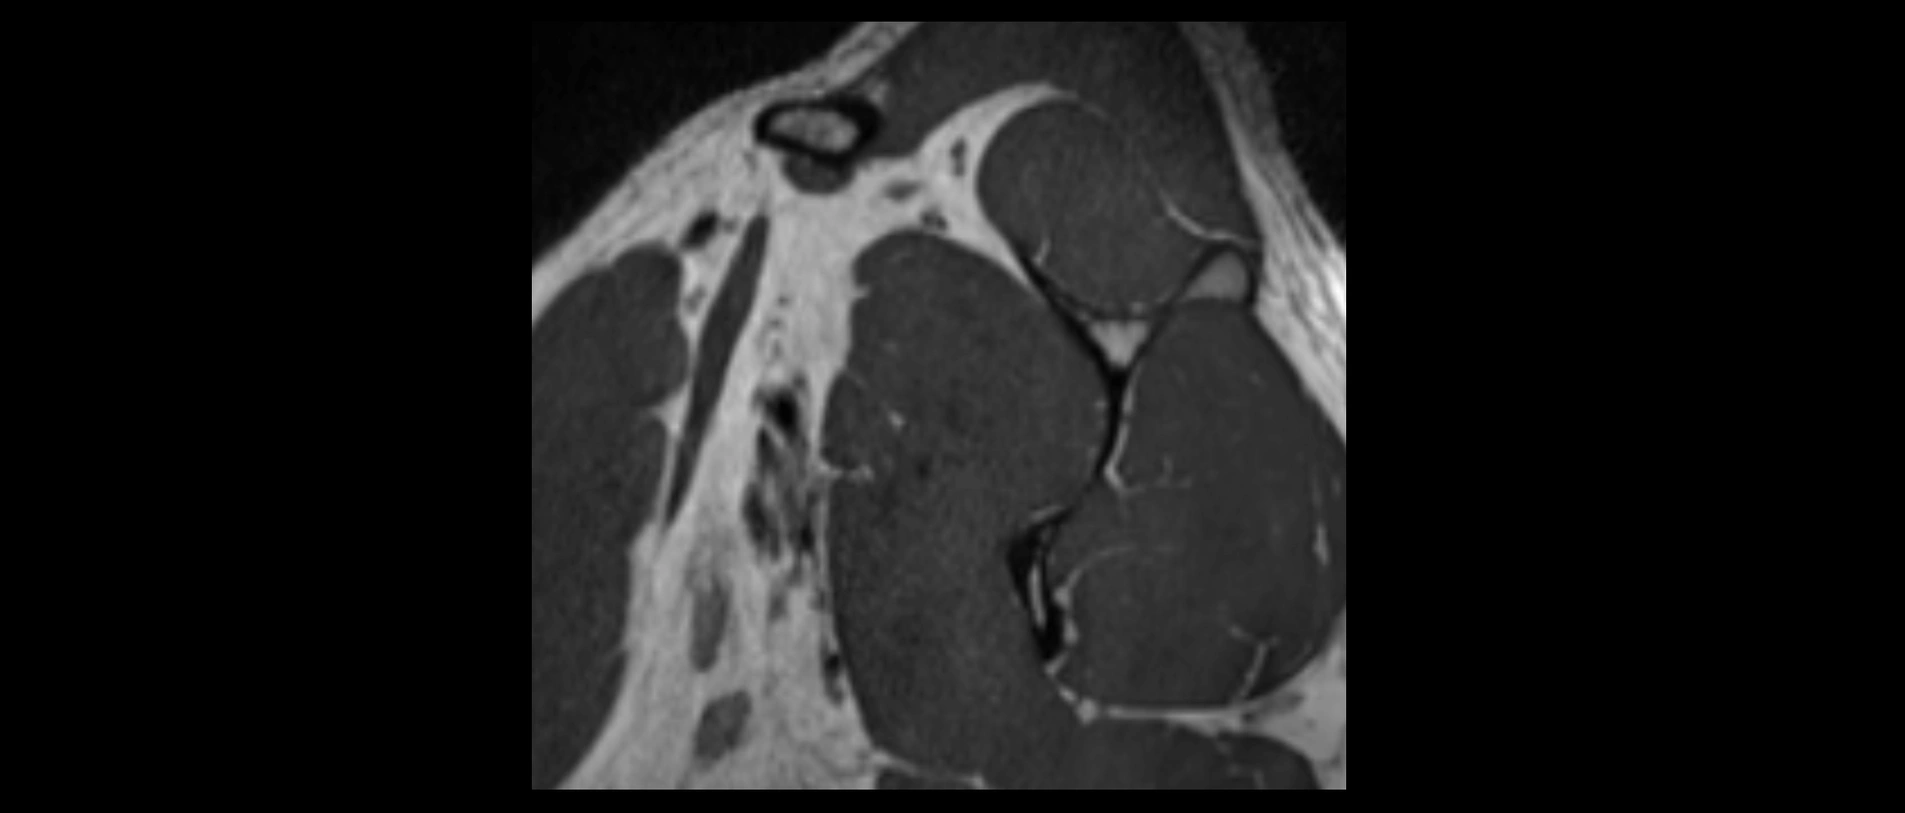

MRI images

image